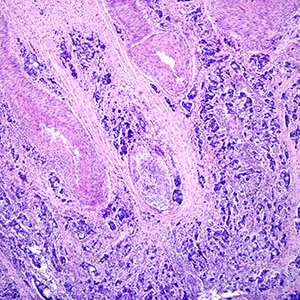

Learn how a Gleason score is calculated to help determine the aggressiveness of prostate cancer, and how it could influence a patient’s treatment.

Doctors examine a tumor in several different ways to determine whether a cancer is aggressive – and what kinds of treatments, if any, might work best.